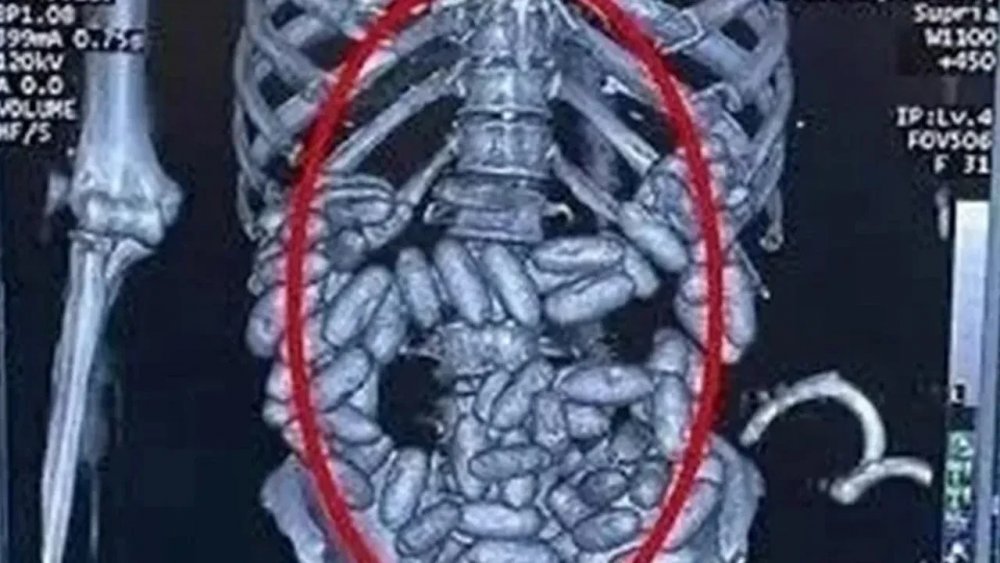

Müldür'ün kuryelerinden Nijerya asıllı 22 yaşında bir kadın Sao Paulo'dan havayolu ile İstanbul'a geldiğinde midesinde 1 kilogram ağırlığında olan 82 kapsülle yakalandı.